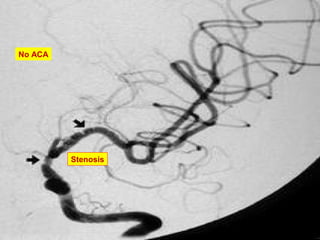

Lateral MRA proximal occlusion of the MCAs &ACAs

Lateral MRA proximalocclusion of the MCAs &ACAs

• #25 Magnetic resonance angiography of the brain of a 44-year-old African American woman demonstrated the absence of the middle and anterior cerebral arteries bilaterally (A). There is also marked hypertrophy of the lenticulostriate arteries bilaterally, which were very large in caliber distally, concurrently revealing collateralization of the posterior cerebral arteries to the anterior cerebral artery distribution over the convexity. Magnetic resonance imaging of the brain also showed the proximal occlusion of the anterior cerebral and middle cerebral arteries (B; indicated by double arrows). The patient, who had recently had a stroke, was diagnosed as having moyamoya disease.

• #26 Lateral view of a magnetic resonance angiography of the brain of a 44-year-old African American woman. The imaging study displayed the proximal occlusion of the middle cerebral arteries and the anterior cerebral arteries. The patient, who had recently had a stroke, was diagnosed as having moyamoya disease.